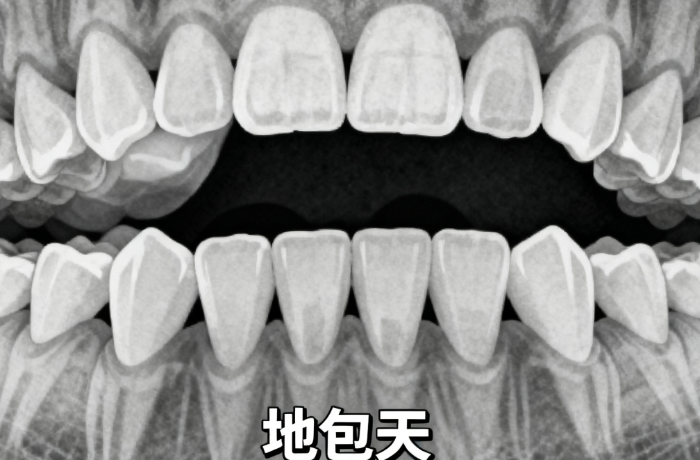

牙齿拥挤度:拥挤较重,可能需要先拔牙

咬合关系:上下牙咬合不正,需要调整